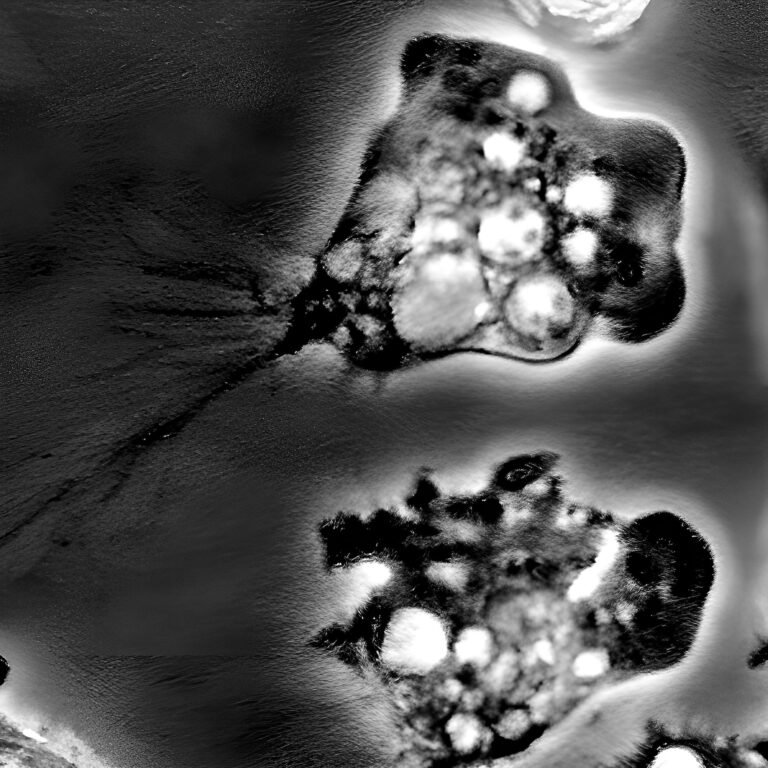

Doctors put the child on a ventilator and began a breakneck effort to find out what was wrong. What they discovered, swimming in the boy’s cerebrospinal fluid, was an organism that left little room for hope: Naegleria fowleri, more popularly known as a “brain-eating amoeba.”

N. fowleri thrives in warm fresh water around 80 degrees Fahrenheit (26.6 degrees Celsius) or warmer, although it might manage to hang on in cooler temperatures, too, according to the CDC. It infects people purely by accident, when water is forced up the nose, driving the amoeba through a lacy bone called the cribriform plate to the olfactory nerve, which acts as a highway to the brain.

PAM kills by massive destruction of brain tissue. The amoeba itself does some of the destruction directly, giving it the “brain-eating” moniker, but much of the brain damage is actually caused by the body’s aggressive immune response to an intruder in the control system, Conrad explained. Parasites that evolve to live inside a body usually have ways of tamping down their host’s immune response so they don’t lose their meal ticket, Conrad said. But because N. fowleri has no need for a host, it has none of those adaptations. “It’s a bull in a china shop,” Conrad said.

The test for the amoeba is simple: Take a sample of the fluid surrounding the brain and spinal cord and look for swimming single-celled organisms. But doctors may not think to order the test in time, because PAM looks like meningitis caused by much more common viruses and bacteria. Families of children who have died of the disease are increasingly working to raise awareness, which could hopefully spur quicker diagnosis and treatment. For instance, the Jordan Smelski Foundation for Amoeba Awareness, started by the parents of an 11-year-old boy who died of PAM in 2014, hosts educational events for doctors and the public.